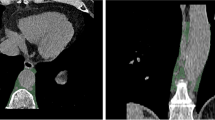

Image evaluation parameters and segmentation

For each patient, abdominal aortic calcification was diagnosed based on computed tomography by a clinically experienced radiologist on specially reconstructed virtual non-contrast enhanced images (I.A.), resulting in a classification of patients into two groups with and without abdominal aortic calcification. Segmentations were performed in the open-source software 3DSlicer by a medical student (H.T. with 2 years of experience in segmentation) (Version 4.11) [40]. Abdominal periaortic adipose tissue (AAT) was defined as any voxel between −195 and −45 HU as it was done in previous studies [41]. For segmentation a ring of 5 mm was drawn around the abdominal aorta including the defined voxels (Fig. 1). The region of measurement ranged from below the junction of the renal arteries with the abdominal aorta to the aortoiliac bifurcation. For volumetric evaluation of calcification, the calcifications of the infrarenal aorta were segmented.